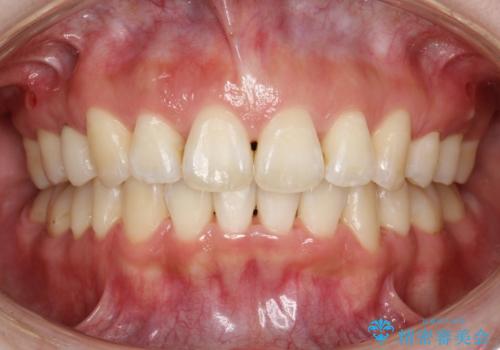

抜歯をして前歯を下げ、ガタつきを取り除く ワイヤー矯正

- 30代女性

- 治療期間

- 1年9ヶ月